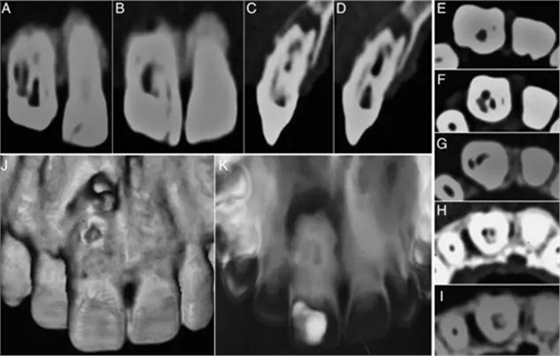

在討論完治療風險和成本等相關(guān)事項后患者簽署了知情同意書。橡皮障隔離,局部麻醉下開放髓腔,去除齲壞和腐爛的牙體組織。在清洗完冠部通道后用牙髓探針DG16來定位根管口。逐漸去除牙膠的同時用3%次氯酸鈉沖洗(圖1C)。隨后在釉牙骨質(zhì)界附近發(fā)現(xiàn)了兩個主要根管開口,并用手用擴孔挫2、3和4擴大。用10#和15#k銼探索直到遇到阻礙。用17%EDTA和3%次氯酸鈉沖洗。在初步?jīng)_洗和暫封后,病人拍攝了CBCT,顯現(xiàn)了牙體內(nèi)部形態(tài)的3維結(jié)構(gòu)(2A–K)。復診在牙科顯微鏡下探查根管,發(fā)現(xiàn)近中根管口通向一個寬的Oehlers III型b的牙內(nèi)陷(MI)。遠中根管口通向2個根管,近遠中根管(DM)根管和遠中根管,還有一個在最遠中部分的盲袋。盲袋是Oehlers II型的第二類牙內(nèi)陷(DI),因為它終止在根中1/3。此外,還發(fā)現(xiàn)了近中切角處一個近中根管(M) (圖3A and B)。一共發(fā)現(xiàn)了5個根管并且他們之間互有交通。所有的根管除了DI都終止于一個大口徑的根尖孔。因此,牙齒被診斷為雙重牙內(nèi)陷,包含Oehlers III型b和II型。牙髓根尖周病變被診斷為慢性根尖膿腫。

圖2:A:腭部近中到遠中可以看到兩個根管(MI和D)和一個盲袋;B:唇部可以看到另外兩個根管(M和DM);C和D:矢狀面可以看到環(huán)形的牙內(nèi)陷;E:寬髓室和窄M根管;F:4個根管,分別命名為M、MI、DM、D;G:盲袋DI;H:根尖有兩個根管口;I:大口徑根尖孔;J:3維上頜牙弓唇部形態(tài);K:牙內(nèi)陷腭部形態(tài)。